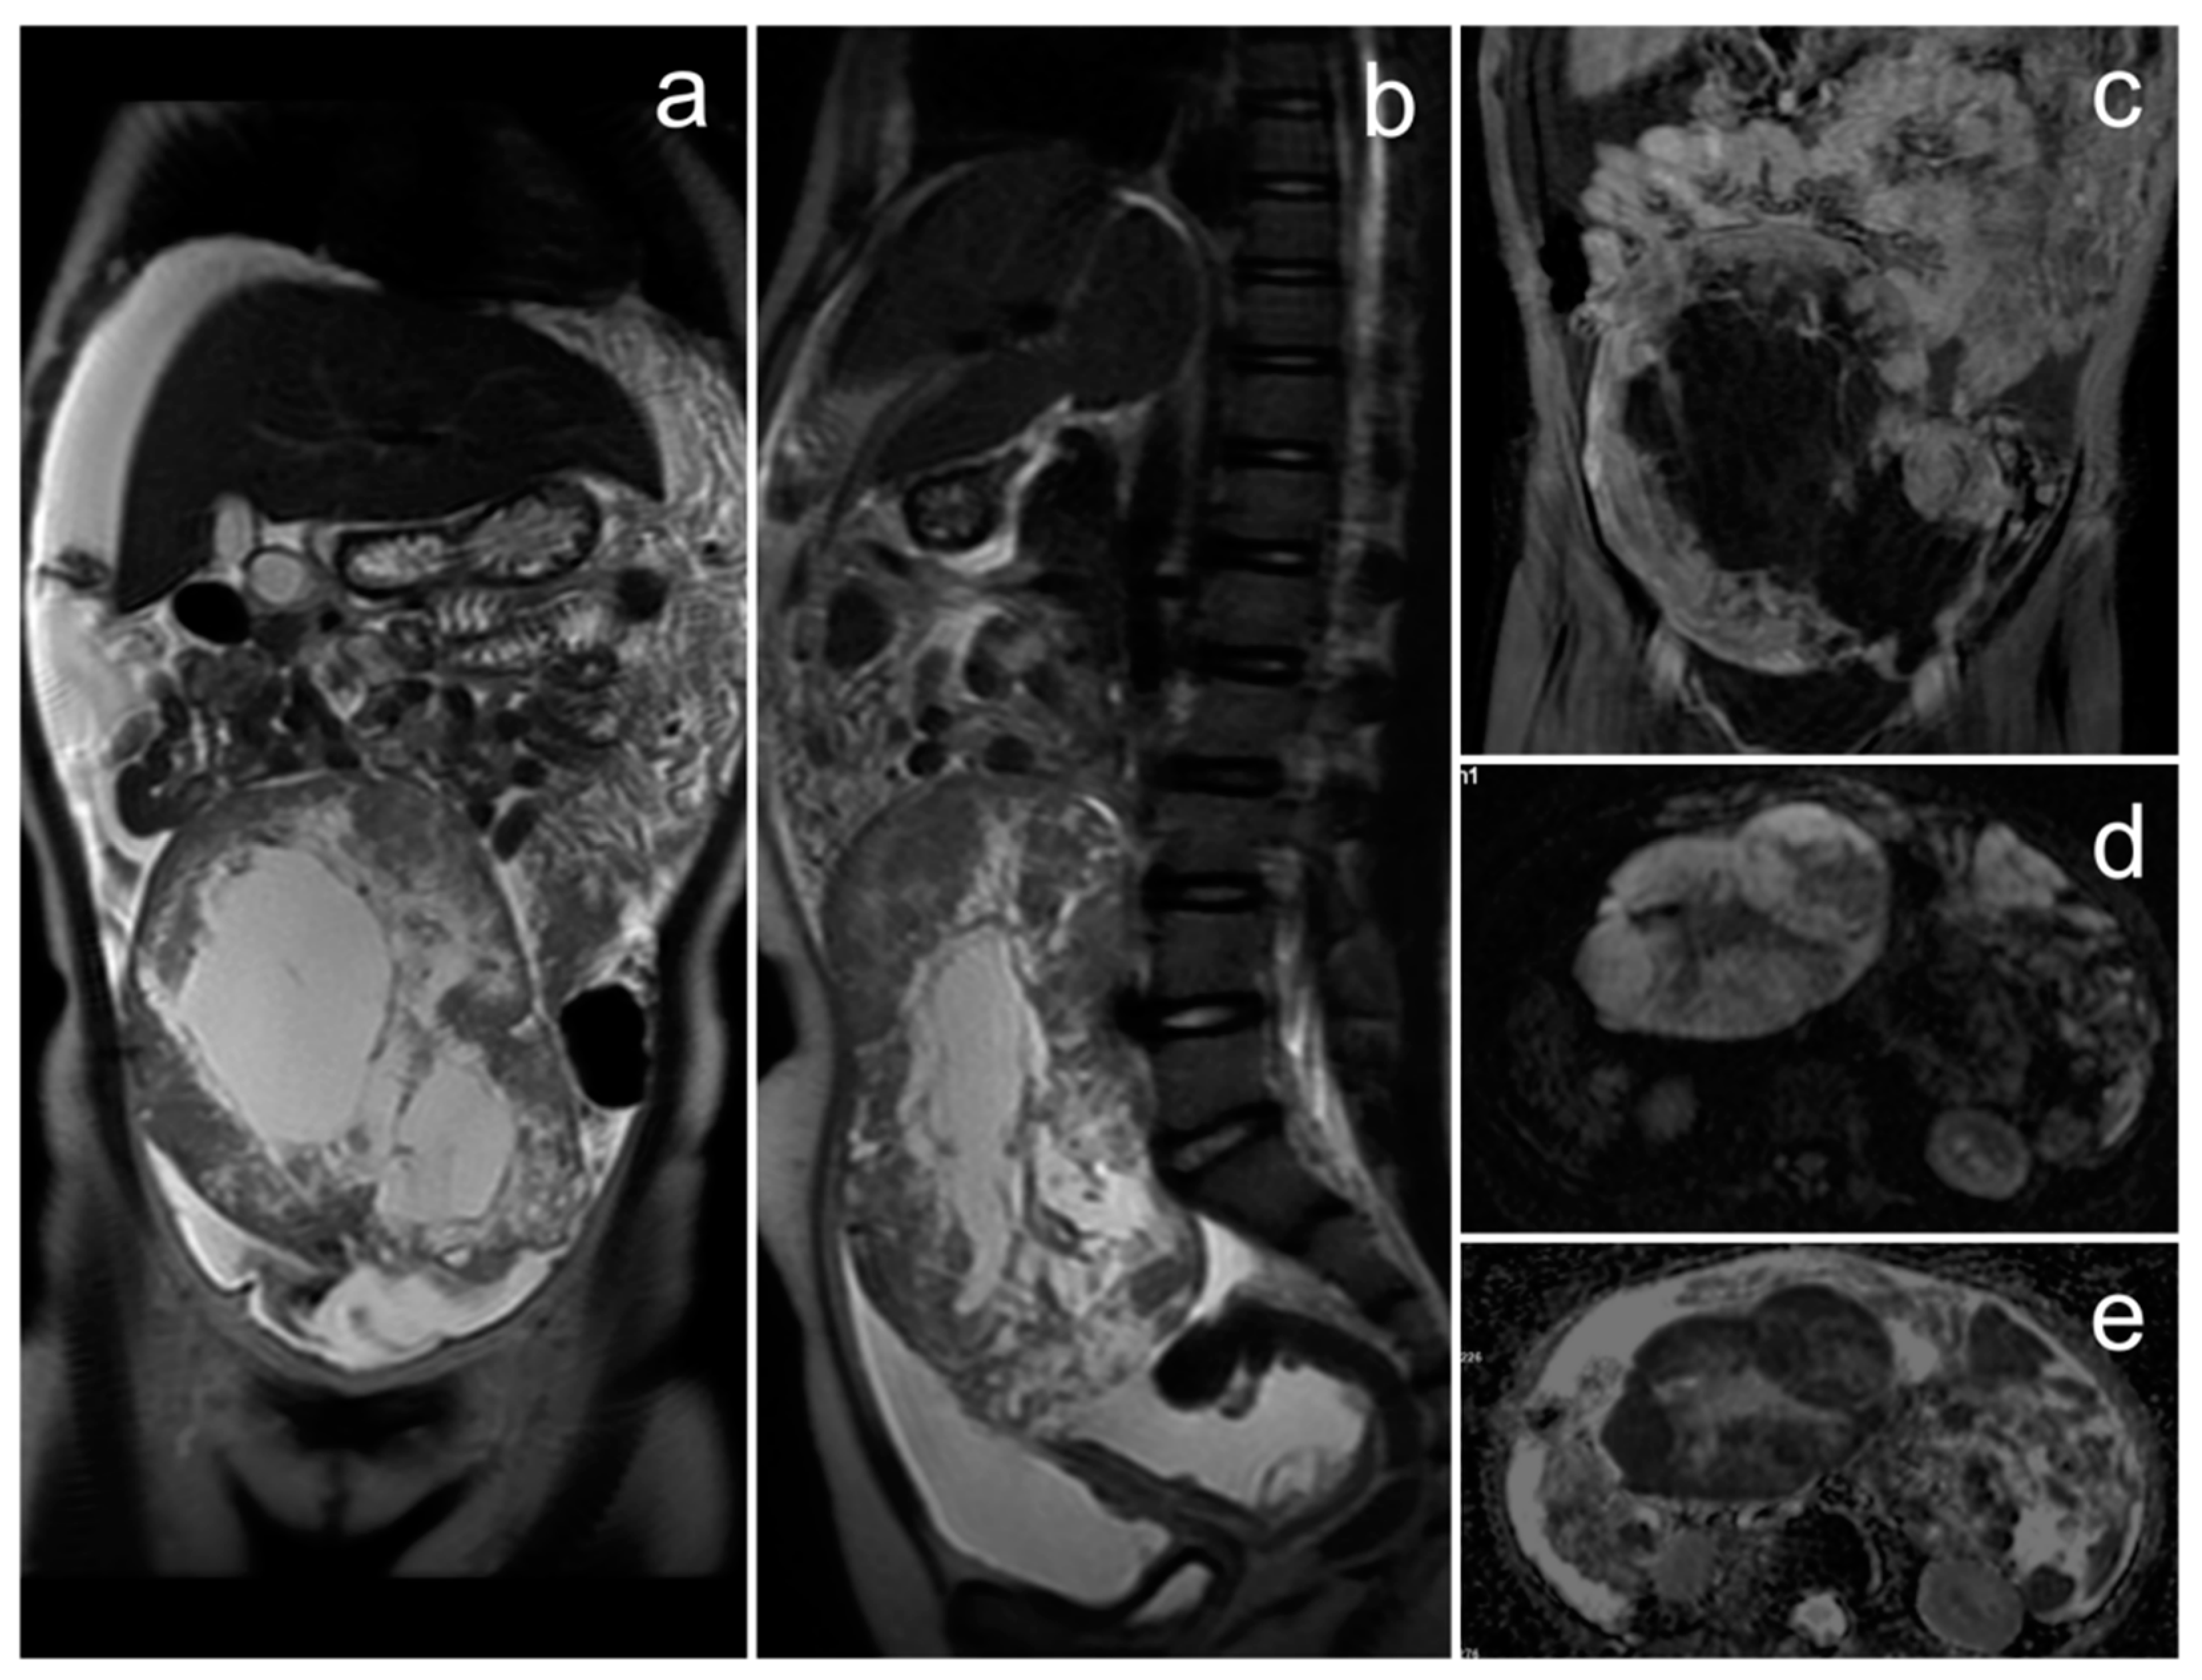

3.1. Small Cell Carcinoma of the Ovary, Hypercalcemic Type

Case Report

| Small cell carcinoma of the ovary, hypercalcemic type | non-specific; unilateral, sizable mass with central necrosis or calcifications | hypercalcemia | symptoms associated with hypercalcemia: polydipsia, constipation, polyuria, bone pain, muscle weakness |

| Ewing sarcoma/primitive neuroectodermal tumor of the ovary | variable; three MRI patterns: (1) large, solid, heterogeneous tumor with restriction diffusion and varying degrees of contrast enhancement, (2) mass consisting of thick-walled cystic lesions with numerous septa, (3) combination of (1) and (2) | - | non-specific; abdominal/pelvic pain, mass in the abdomen/pelvis, weight loss, bloating, irregular periods, abnormal vaginal bleeding, back and lower limb pain |